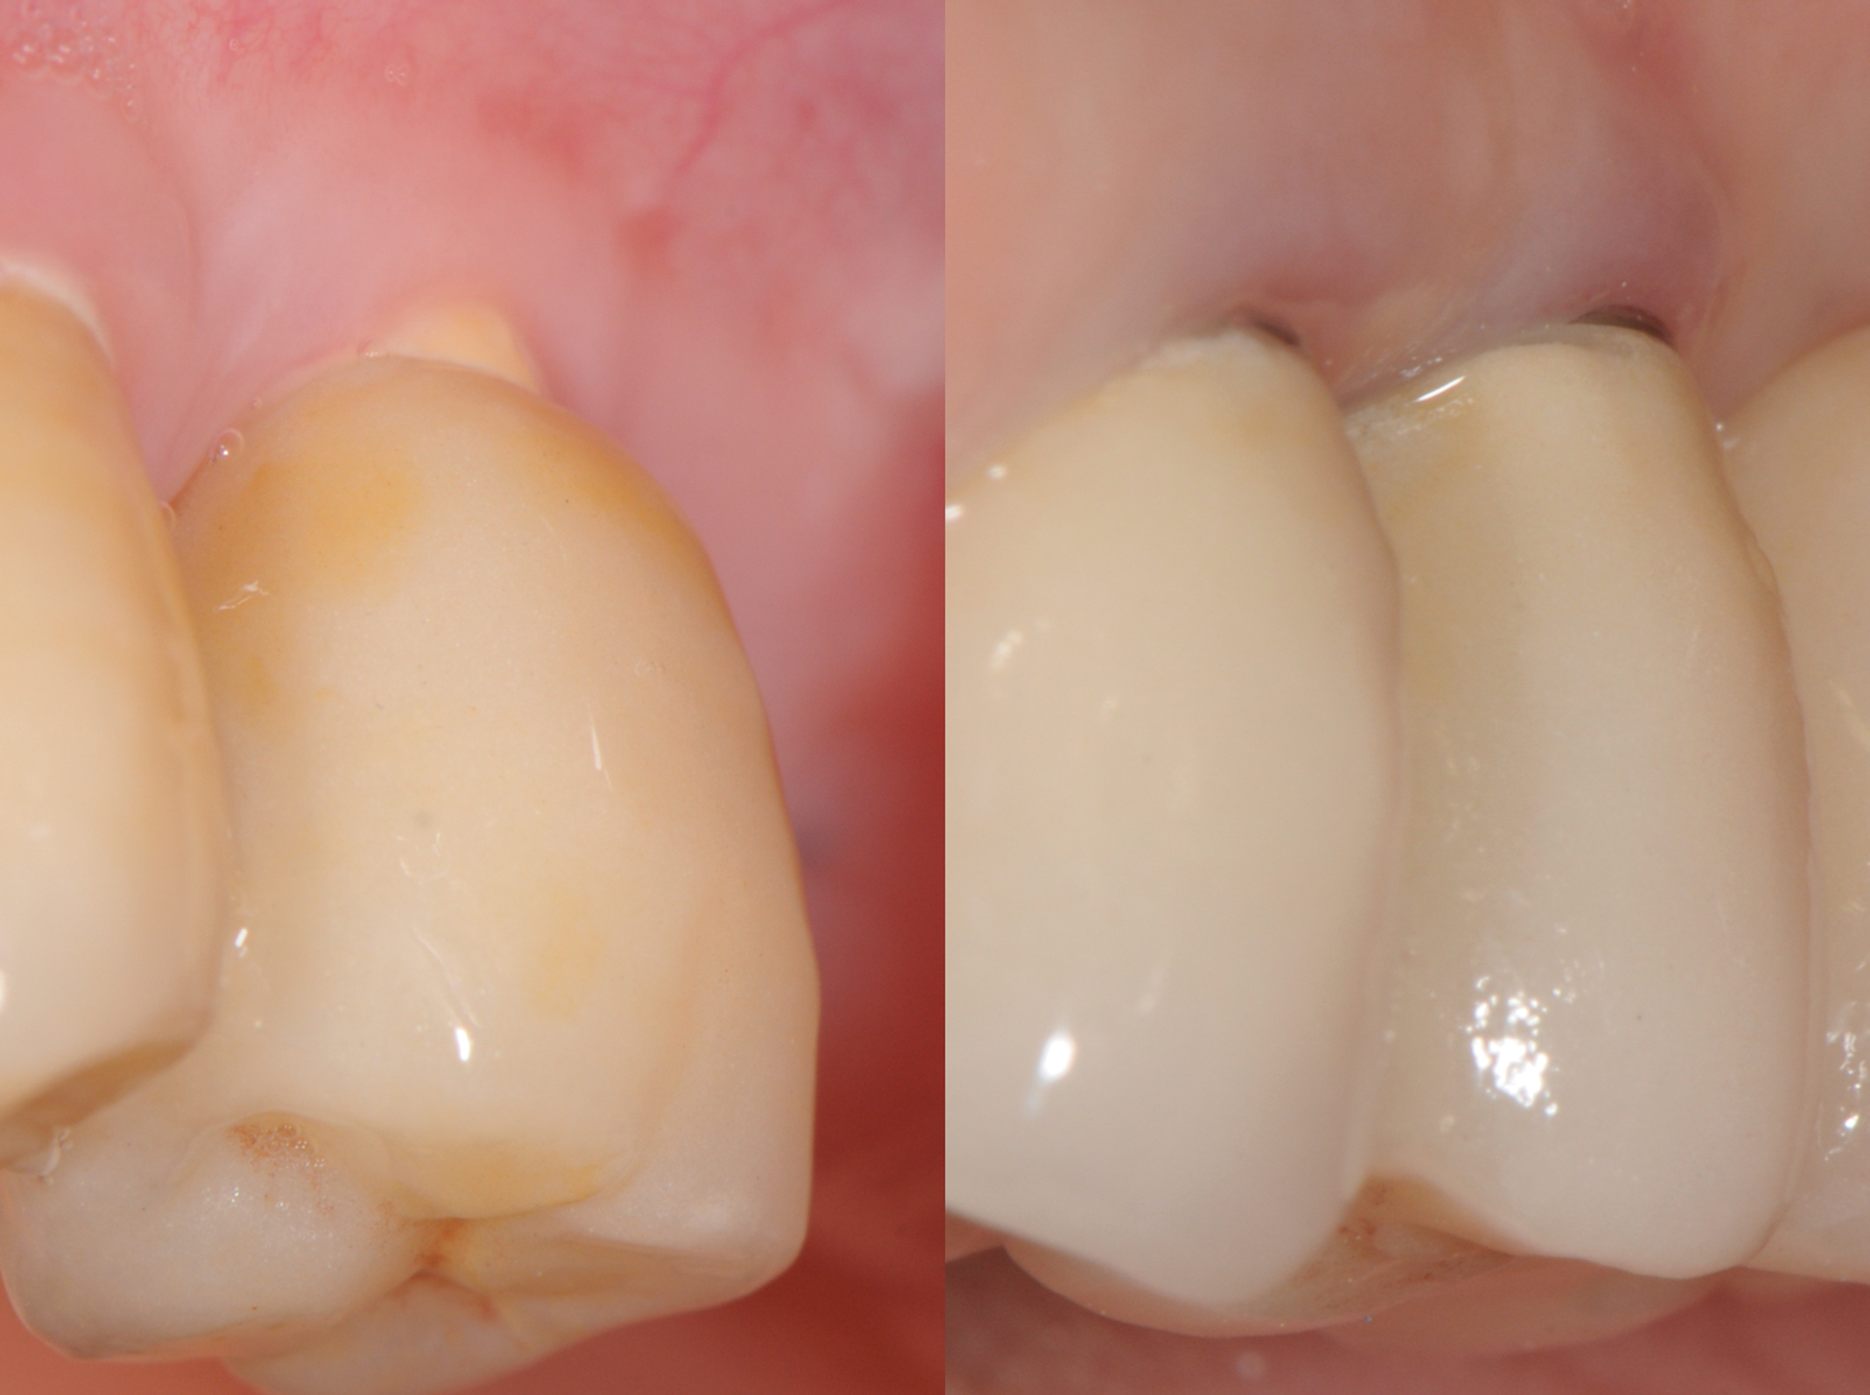

Fig 2. Recessions in ceramic (left) and titanium (right) implants.

Figure 2

Still, as with titanium implants, undesirable recession with an exposed implant shoulder may occur in rare cases with ceramic implants. Nonetheless, from an esthetic point of view, this inflammation-free recession of the gingiva is likely to be tolerated much better by patients concerned with the dark margins of titanium implants (Figure 2).